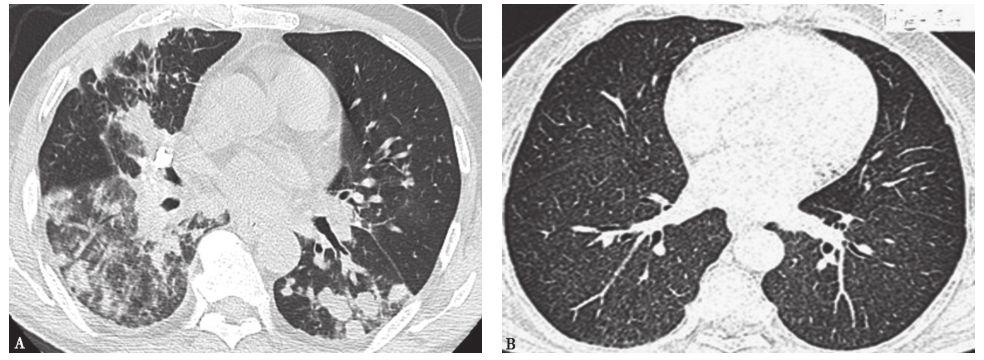

图6隐球菌肺炎胸部CT表现

A.男性患者,73岁,反复发热、咳嗽、咳痰2年,再发1个月,病理确诊为隐球菌肺炎,胸部CT可见双肺多发高密度斑片影,部分呈结节状改变,伴双侧少量胸腔积液;B.男性患者,65岁,反复发热伴消瘦5个月,感染HIV,病理诊断为播散性隐球菌肺炎,胸部CT发现双肺呈随机分布的弥漫粟粒性结节